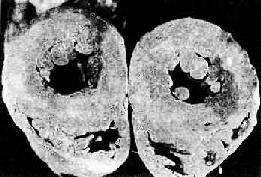

高血压病时左心室向心性肥大(心脏横断面)

图8-11 高血压病时左心室向心性肥大(心脏横断面)

左心室壁增厚,乳头肌显著增粗